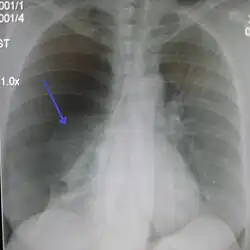

-

Anteroposterior inspired X-ray, showing subtle left-sided pneumothorax caused by port insertion -

Lateral inspired X-ray at the same time, more clearly showing the pneumothorax posteriorly in this case -

Anteroposterior expired X-ray at the same time, more clearly showing the pneumothorax in this case -